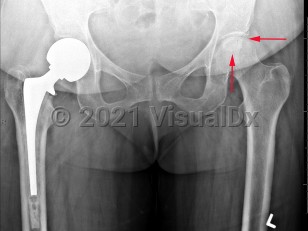

Grade / classification system: The Ficat classification system is based on plain x-rays and the patient's symptoms.

- Stage 0: normal x-rays, asymptomatic; "silent hip" if patient has known contralateral AVN

- Stage I: normal x-rays or subtle trabecular blurring or osteopenia; pain and limited hip range of motion

- Stage II: normal contour of the femoral head but with cystic or sclerotic evidence of bone remodeling; worsening clinical signs

- Stage III: "crescent sign," abnormal contour or flattening of the femoral head from subchondral collapse with joint space preserved

- Stage IV: degenerative osteoarthritis with narrowed joint space and osteophytes; progressively diminished hip motion